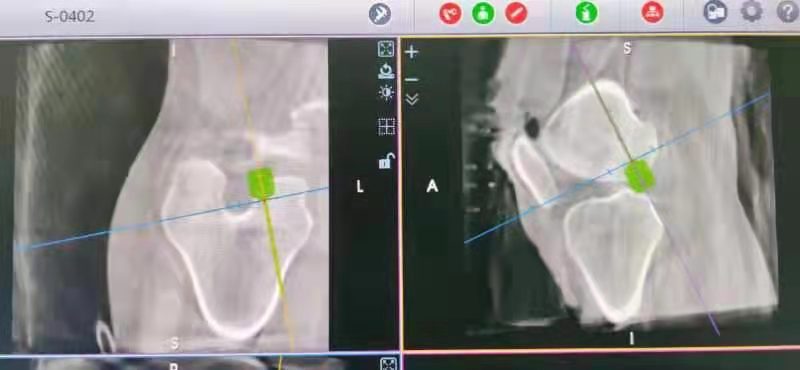

術(shù)中經(jīng)3D-C臂掃描、數(shù)據(jù)采集、三維立體成像后,運(yùn)用機(jī)器人系統(tǒng)軟件規(guī)劃出韌帶重建過(guò)程中骨隧道導(dǎo)針的出入點(diǎn)和方向,經(jīng)自動(dòng)數(shù)據(jù)化處理,計(jì)算出符合醫(yī)生要求的手術(shù)三維路徑,發(fā)送指令使機(jī)械臂自動(dòng)移動(dòng)至最佳位置,建立精準(zhǔn)的骨隧道,完成手術(shù)操作。本次手術(shù)用時(shí)約60分鐘,術(shù)中出血約20ml。術(shù)后,患者膝關(guān)節(jié)活動(dòng)度及穩(wěn)定性獲得了令人滿(mǎn)意的效果。

3D-C臂掃描 數(shù)據(jù)采集

機(jī)器人輔助定位